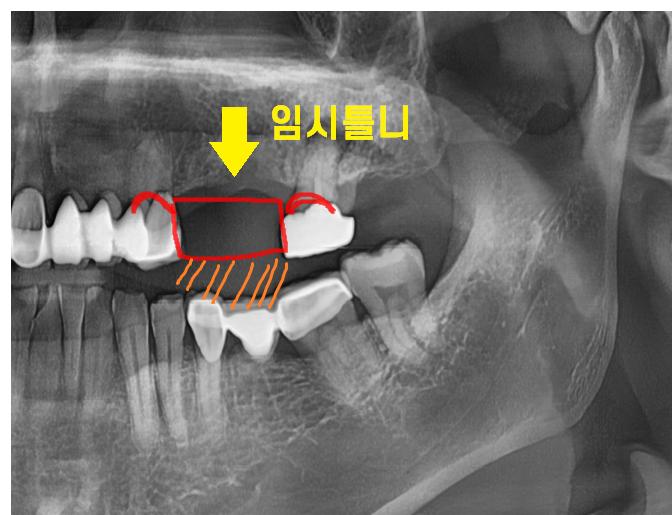

231017

이럴 경우 임플란트 임시 틀니를 만들어

빈 공간을 채워줍니다.

맞닿이게 하여 반대편 치아가 움직이지 못하게

해주는거죠.